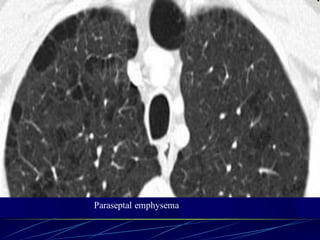

Paraseptal (distal acinar)

emphysema

Affects the peripheral parts of

the secondary pulmonary lobule

Produces subpleural lucencies.

86

Paraseptal emphysema